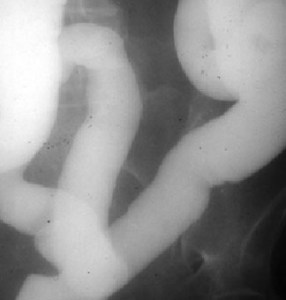

Otro paciente con esprúe avanzado mostrando este signo. La apariencia de las asas intestinales en la radiografía se ha equiparado también al aspecto de la pasta de dientes.

SIGNO DEL MOLDE

Recibe este nombre el aspecto de la luz del yeyuno en el esprúe avanzado o no tratado, en el estudio de tránsito intestinal baritado. Los pliegues mucosos aparecen borrados y el bario que llena la luz del intestino adopta la forma de un tubo relleno de cera endurecida. Habitualmente se asocia a segmentación marcada e hipersecreción (que no están presentes en esta imagen, que es una fotografía localizada en fosa iliaca izquierda de un tránsito intestinal).

En la literatura médica no es infrecuente encontrar este signo con su nombre original en francés: moulage o Signo del moulage.